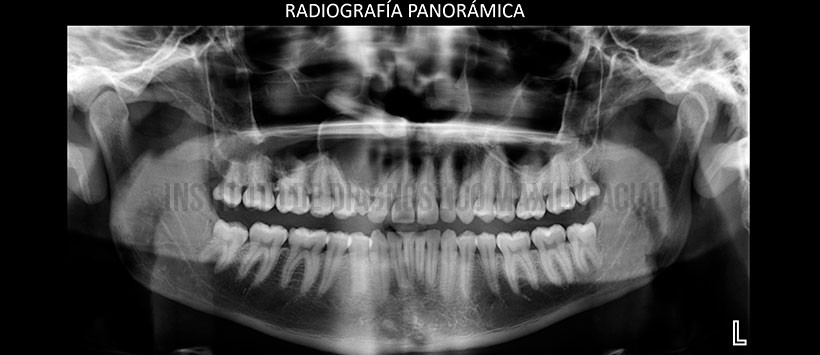

En la evaluación mediante la radiografía panorámica se aprecia una neumatizacion alveolar de ambos senos maxilares, apiñamiento dentario anterior y piezas 38 y 48 retenidas. Siendo lo mas resaltante una imagen radiolúcida localizada en zona anterosuperior de lado derecho, de limites definidos y bordes corticalizados ocasionando un desplazamiento hacia cefálico de la pieza 13, parte de las paredes de seno maxilar de ese mismo lado y divergiendo los segmentos radiculares de las piezas 11, 12, 53, 54, y 55. (Figura 2)